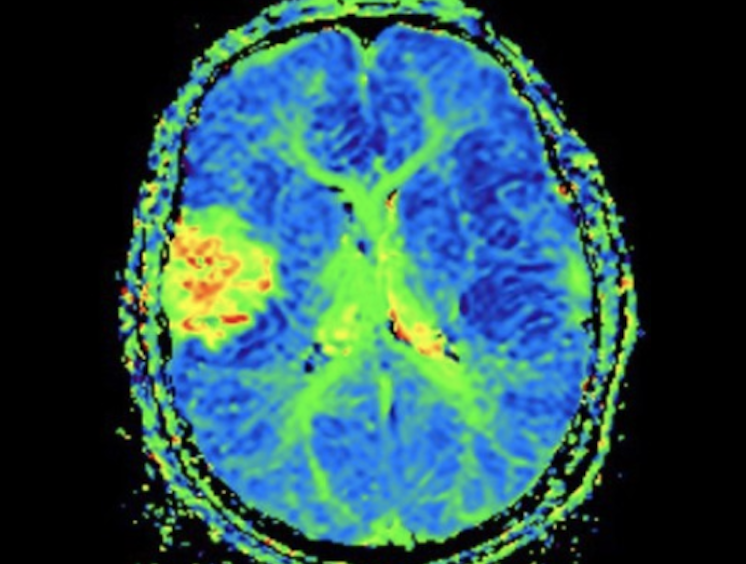

In the past, MR Innovations and SpinTech have worked closely to create innovative technology for products such as STAGE, a standardized MRI software program allowing for improved efficiency and AI-assisted detection. STAGE technology allows for up to 40% faster MRI acquisition times for brain scans, improved visualization, and quantitative results with applications across conditions such as Parkinson's disease, dementia, traumatic brain injury, multiple sclerosis and stroke.